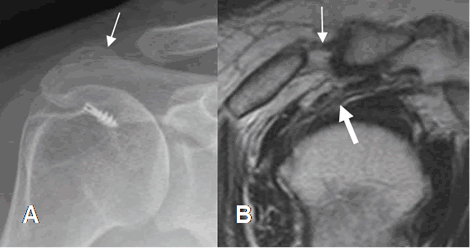

Los cambios incluyen alteración en la morfología del acromión y el ligamento coracoacromial y aumento de la distancia acromioclavicular. (29). (Fig 158).

Fig 158. Cambios PostQx.

A: Rx AP. Remodelación del acromión, por acromioplastia. Se aprecia material Qx, por reconstrucción del manguito rotador.

B: RM sagital en T2. Aumento del espacio acromioclavicular como resultado PostQx. Existe ruptura parcial del tendón del supraespinoso, el cual es hiperintenso y está adelgazado. (Flecha gruesa).